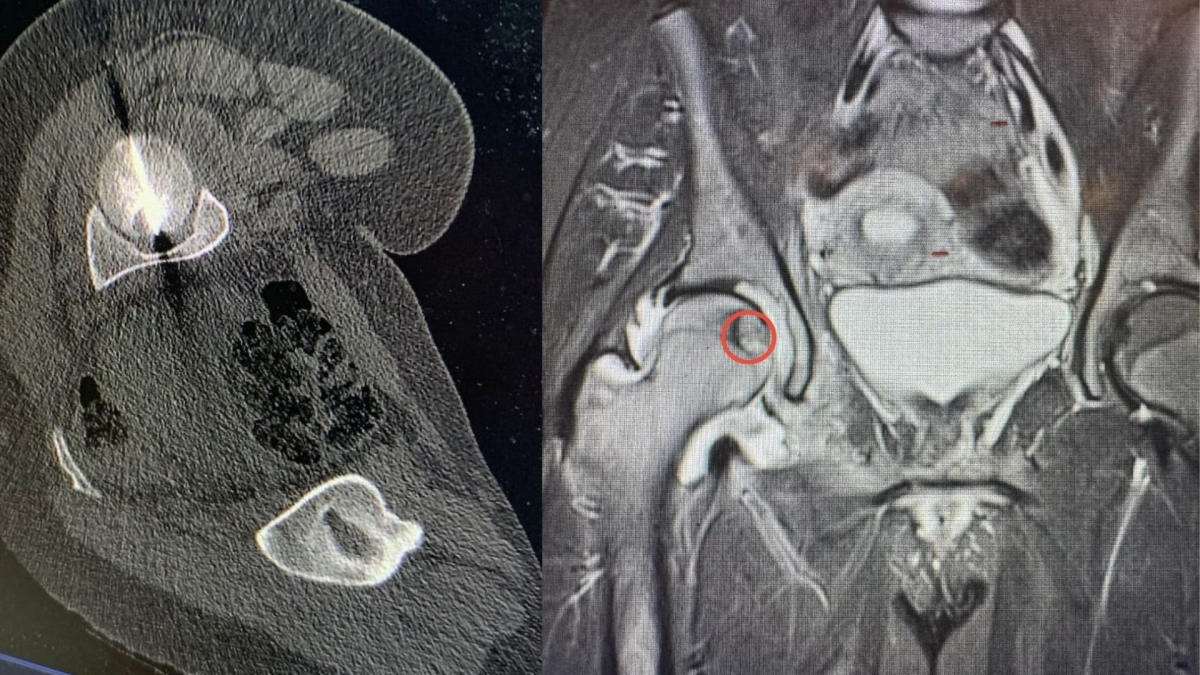

أجرى مستشفى الجامعة الأردنية، تدخلا علاجيا متقدما في قسم الأشعة، استطاع من خلاله فريق طبي متعدد الاختصاصات معالجة ورم عظمي في موقع شديد الحساسية داخل رأس عظم الفخذ لمريض ثلاثيني.

ويعد هذا الموقع من أكثر المواضع صعوبة في الوصول إليها جراحيا، ما يجعل الخيارات التقليدية محدودة ويزيد من تعقيد التعامل مع الحالة، لاسيما وأن المريض كان يعاني من آلام حادة أثرت بشكل كبير على قدرته على الحركة وممارسة أنشطته اليومية.

وبين البطوش، أن الفريق الطبي نجح في الوصول إلى مركز الورم بدقة عالية باستخدام تقنية التصوير الطبقي المحوري (CT Scan)، تلا ذلك إجراء الكي بالتقنية الحرارية باستخدام المايكروويف، وهي من أحدث التقنيات العالمية في علاج أورام العظام دون الحاجة إلى التدخل الجراحي المفتوح.

وأضاف، إن المريض أظهر تحسنا فوريا وملحوظا منذ اليوم التالي للإجراء، ما يعكس دقة التقنية وفاعليتها في استهداف الورم وتخفيف الألم بسرعة وتمكين المريض من استعادة الحركة بصورة أفضل.